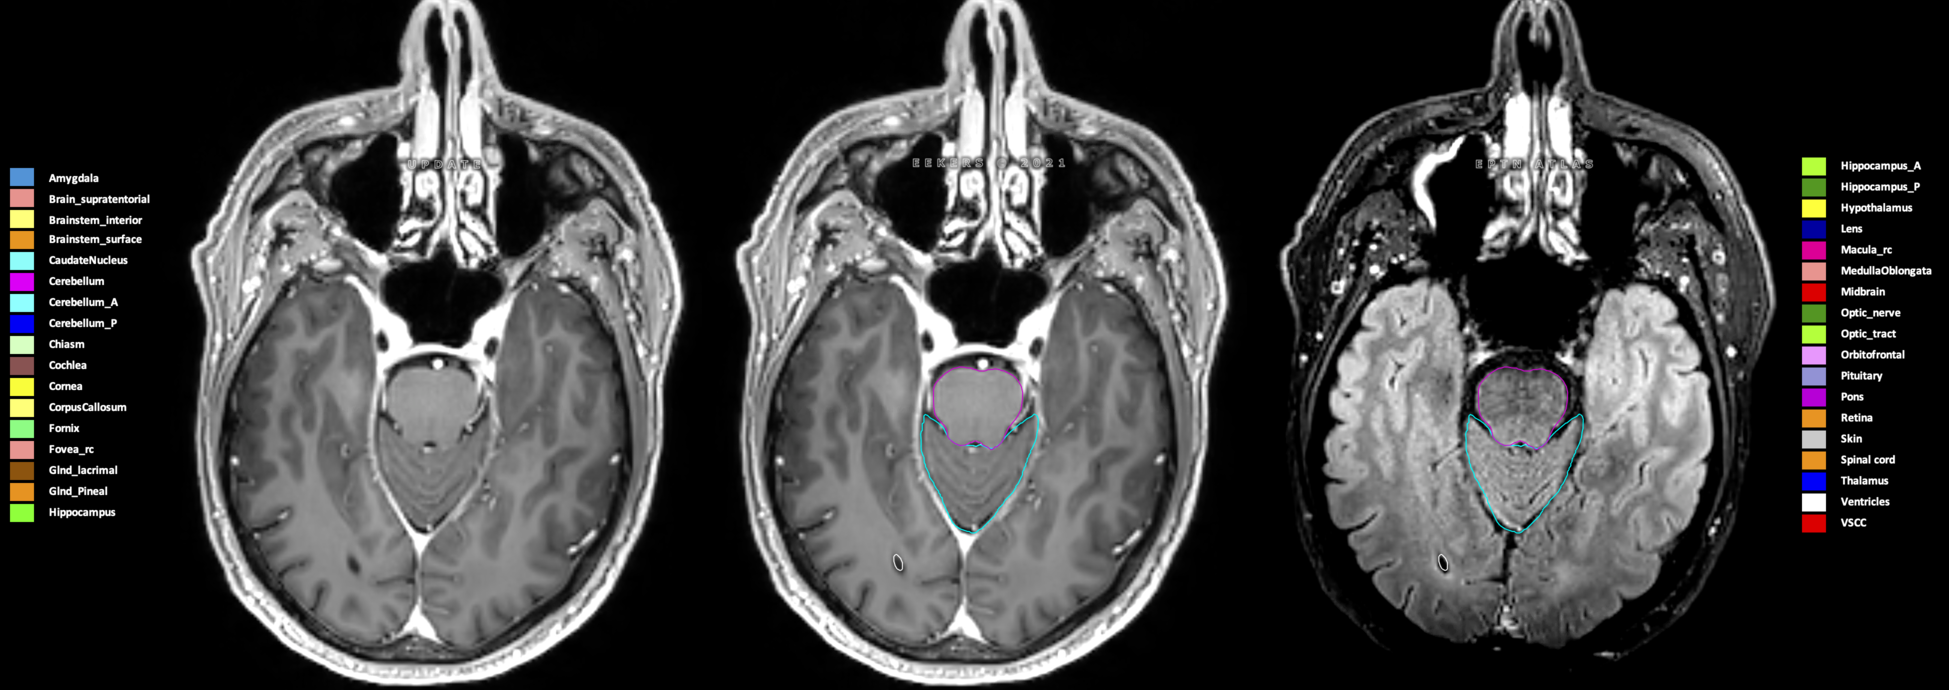

Eekers et al. have published an international neurological atlas for contouring of organs at risk in consensus with the European Particle Therapy Network (EPTN) in 2018 and an update in 2021. The purpose of this consensus atlas is to decrease inter- and intra-observer variability in delineating OARs relevant for neuro-oncology.

Included are all OARs known to be relevant for radiation-induced toxicity in neuro-oncology: brain, brainstem (midbrain, pons, medulla oblongata), chiasm, cerebellum (anterior & posterior), cochlea, cornea, hippocampus (anterior & posterior), hypothalamus, lens, lacrimal gland, optic nerve, pituitary, skin, and vestibular & semicircular canals. To further facilitate research on cognition, vision and radiological changes after irradiation of the brain, potential clinically-relevant OARs are included: amygdala, caudate nucleus, cerebellum (anterior & posterior), corpus callosum, fornix, macula, optic tract, orbitofrontal cortex, periventricular space (PVS), pineal gland, and thalamus.

Three-dimensional delineation of the 25 consensus OARs for neuro-oncology are shown on CT (WW/WL 120/40, 3000/600), 3T MR images, (T1Gd, T2FLAIR 1mm) and 7T MR (MP2RAGE 0.7 mm). All are presented in transversal, sagittal and coronal view.